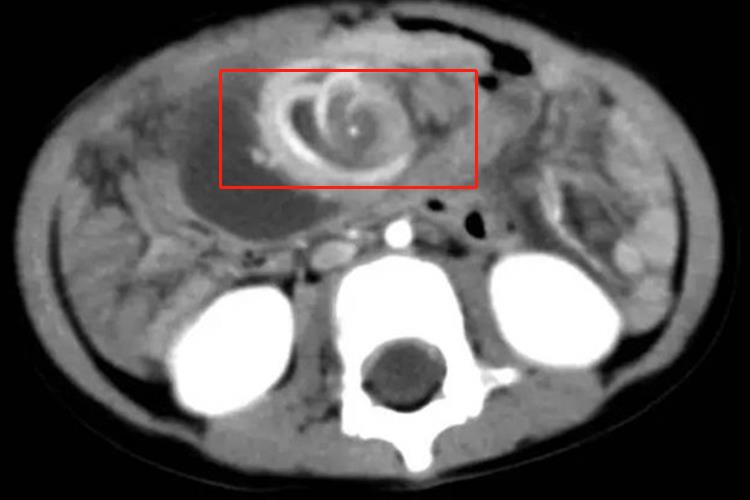

肠扭转的患者在CT检查上可能会出现旋涡征,是肠扭转在CT上的特异性征象,表现为扭曲肠襻及肠系膜周围见放射状分布充血血管。

对于出现肠扭转的患者,会表现为突发持续性腹部剧痛,阵发性加重,脐周疼痛,可放射至腰背部,还会出现频繁呕吐。肠扭转的患者腹部CT扫描,可以看到肠梗阻的表现,还可见典型的系膜扭转表现。漩涡征是肠扭转在CT上的特异性征象,表现为扭曲肠襻及肠系膜周围见放射状分布充血血管影像,扭转肠管的输入段及输出段向肠管扭转处锥形变细。